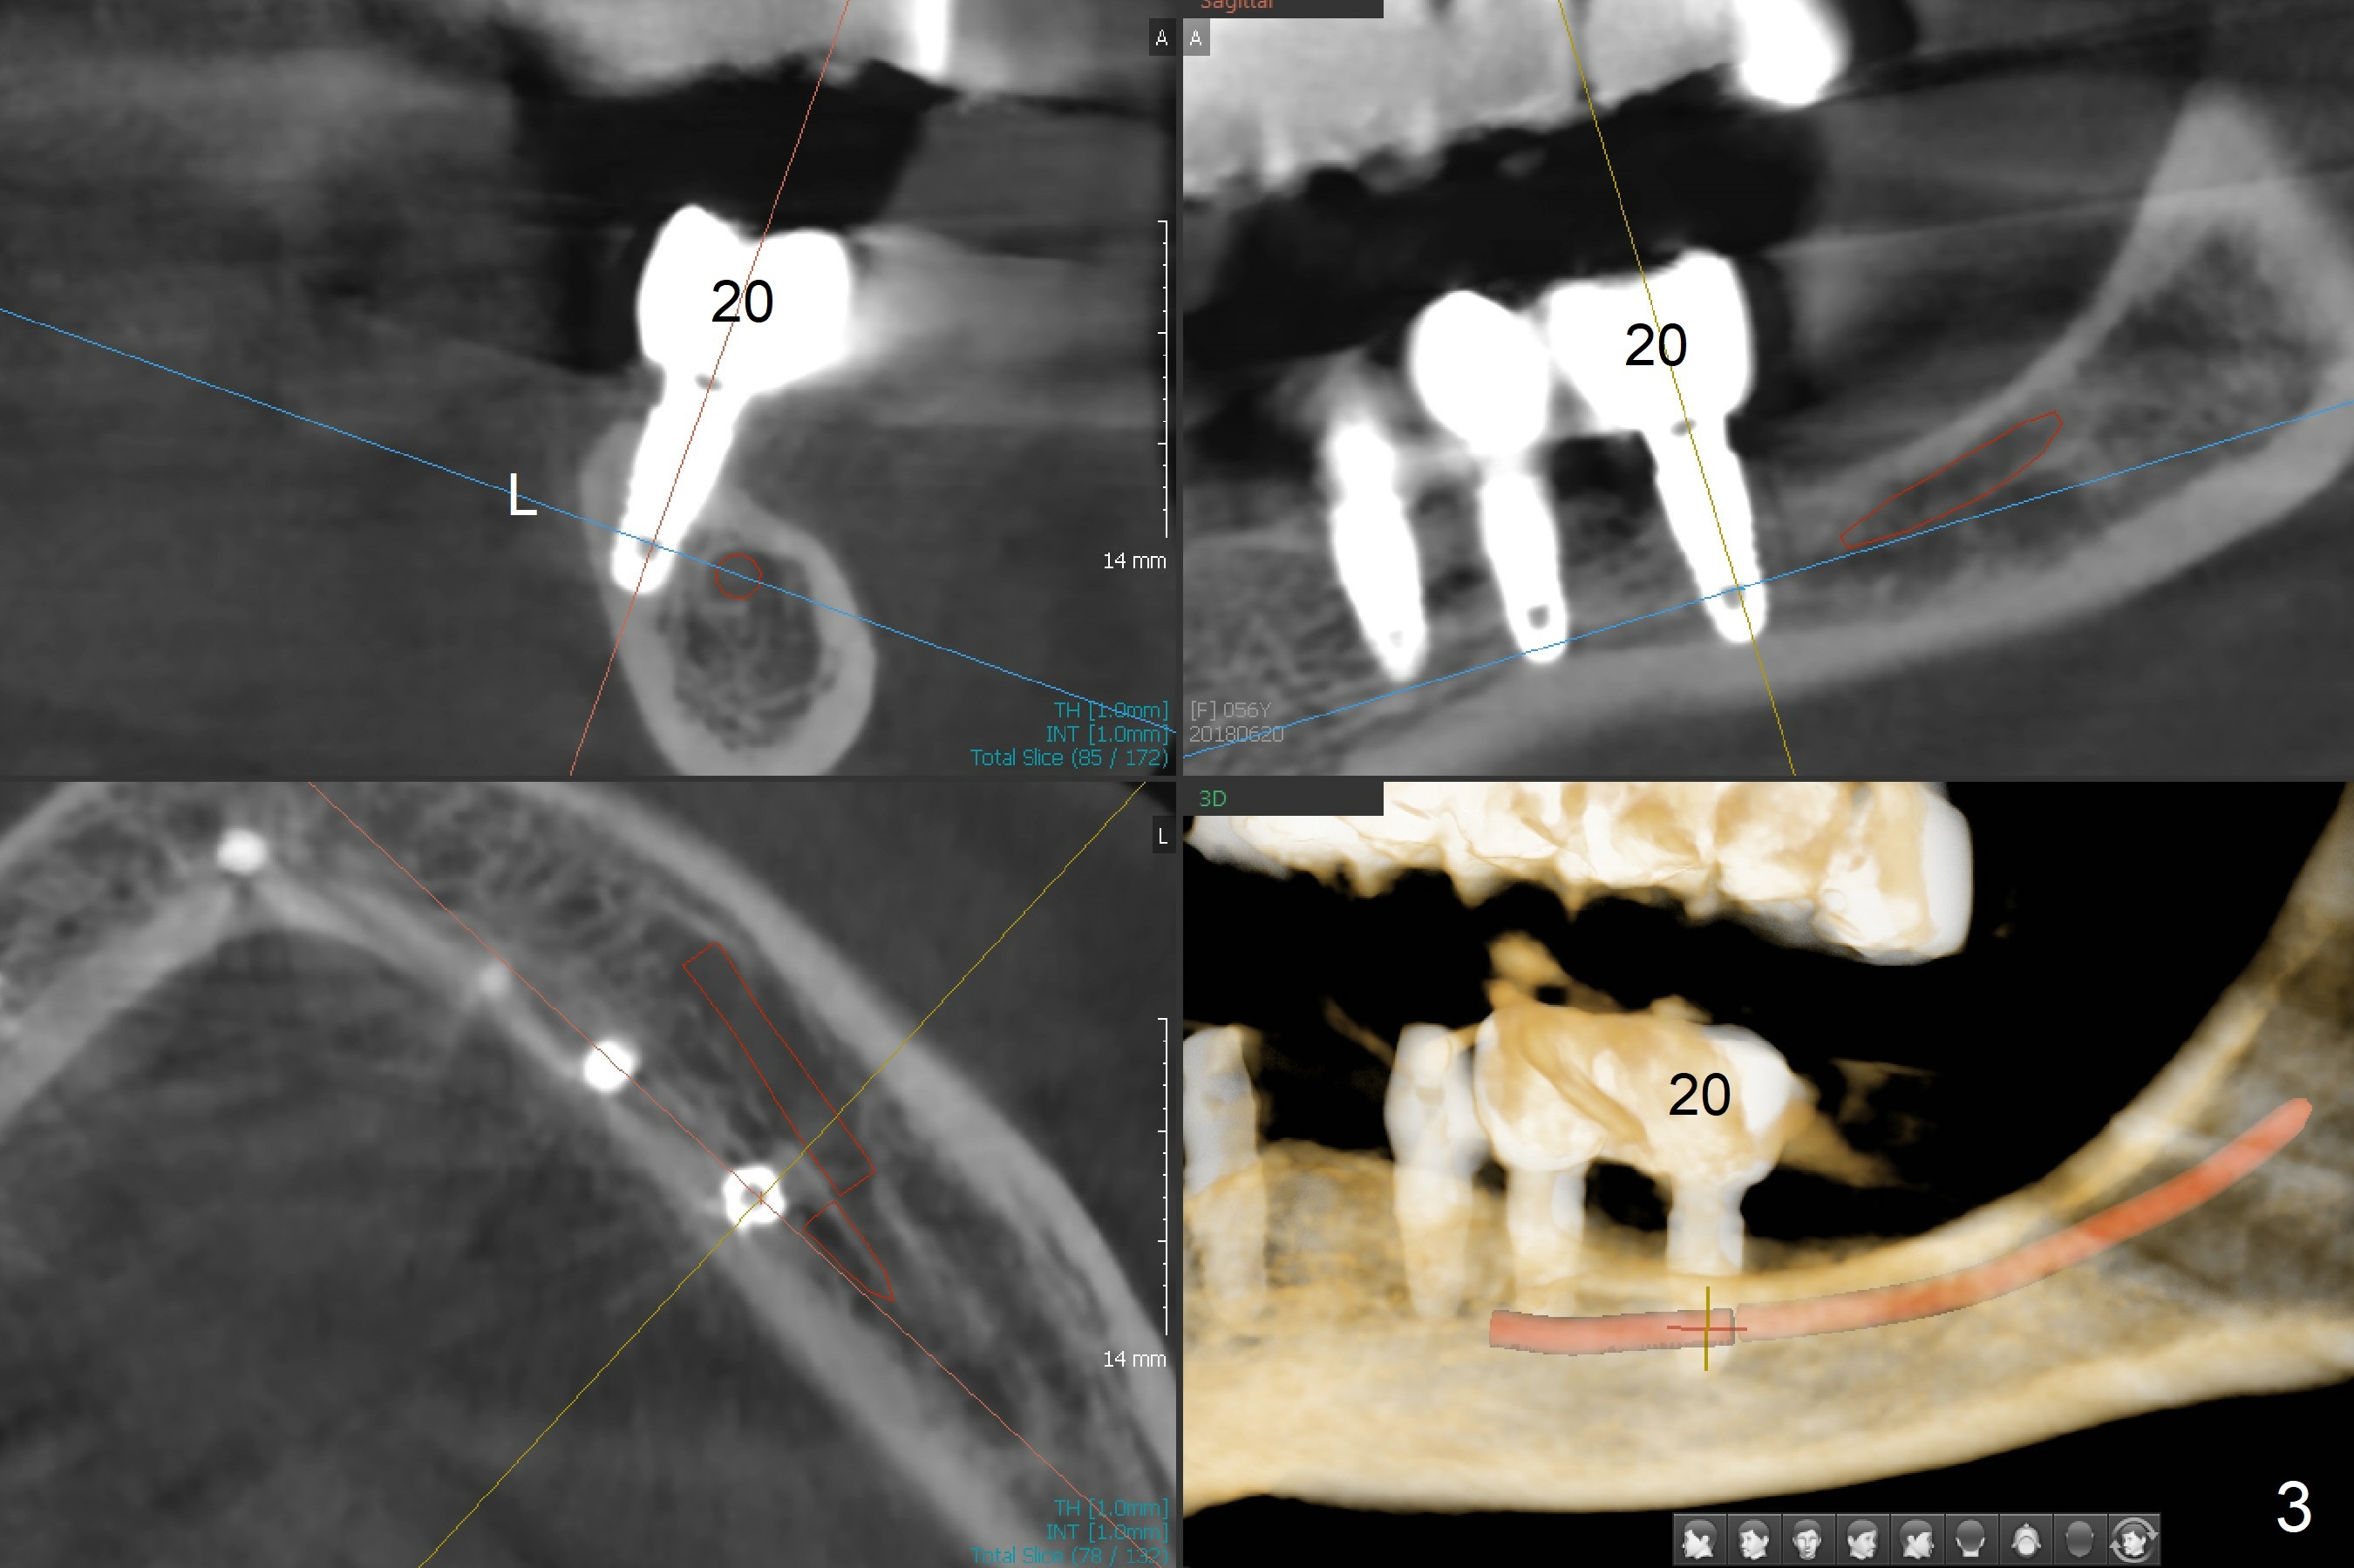

A 56-year-old woman with atrophic jaws requests redoing lower implant restoration (in function 1 year) for cosmetic reason and placing an implant at #19 (because she could not masticate on the left, Fig.1). While the 3.8x8.5 mm implants at #31 and 20 are placed lingual (L) to the Inferior Alveolar Canal (IAC, Fig.2,3) "free hand", can a 4x7.3 mm implant (Fig.4 blue outline) be placed buccally (B) at #19 with a guide?